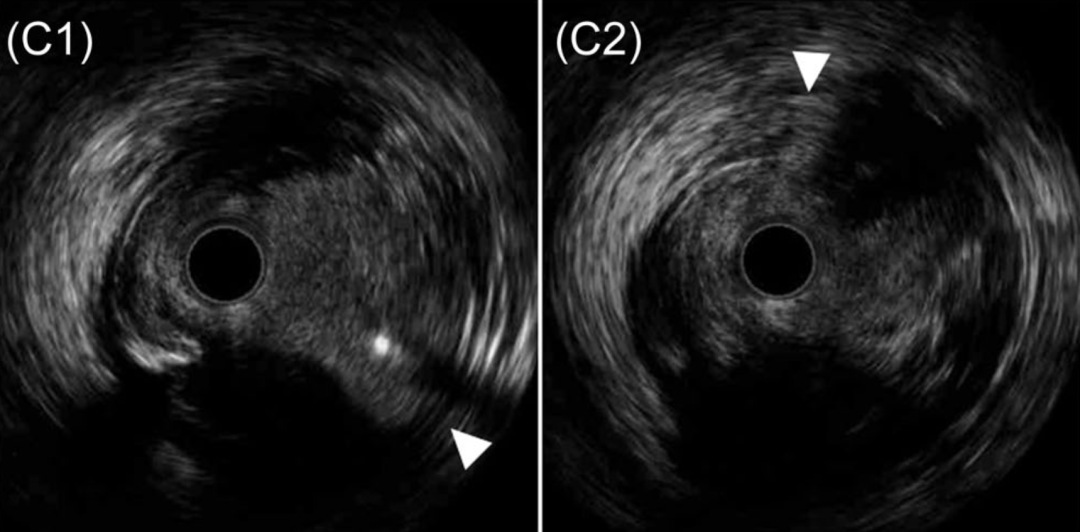

图 3 HDR术后IVUS表现(来自图2病例2)

A、B、C:闭塞RCA的HDR操作。导丝通过后,使用2mm球囊行血管成形术,便于IVUS导管通过。C1–C6:IVUS回撤图像共6个部位:RCA近端伴分支(箭头,C1、C2)、近端纤维帽入口点(箭头,C3)、造影剂充盈的斑块内通道(箭头,C4、C5)、远端纤维帽穿出至真腔(C6)。各部位IVUS导管均位于管腔内。

IVUS证实所有病例导丝均走行于斑块内。(图3)

造影剂(机械或化学地)对病变内组织的修饰作用机制得到了以下观察的支持:HDR后的IVUS成像常常显示闭塞斑块内无回声区,但在其近端或远端则没有(图3),从而支持该机制。